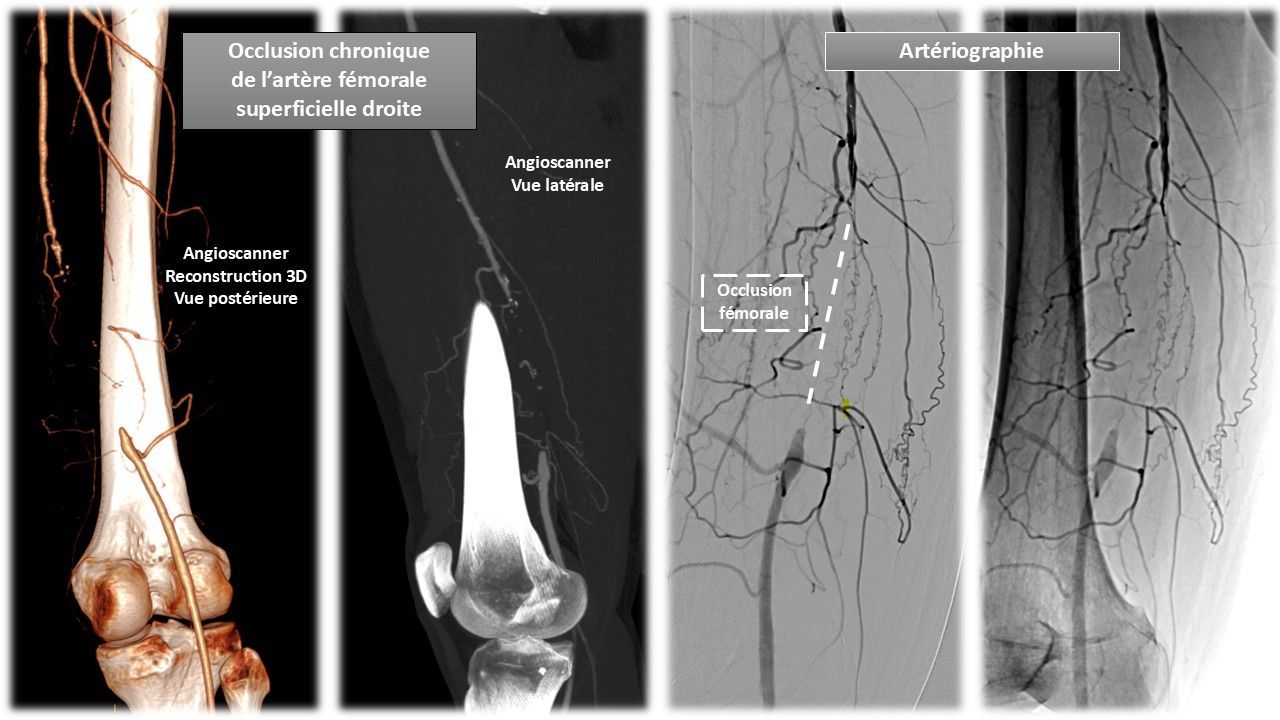

- Artères : artériopathie oblitérante, pied diabétique,